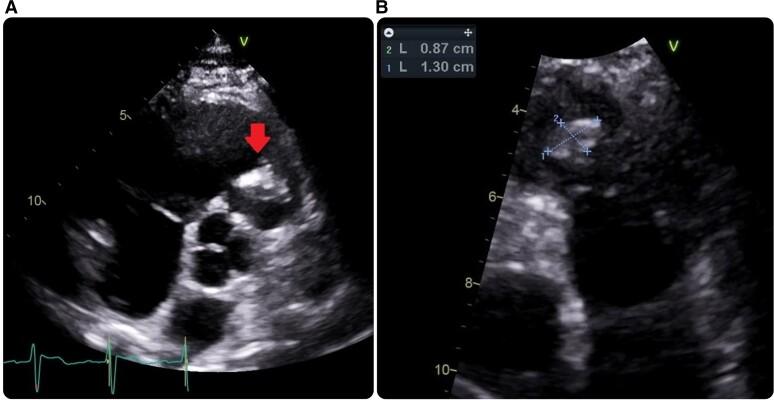

We describe a case of pulmonary valve endocarditis that led to septic pulmonary emboli in a patient scheduled for elective bypass surgery for triple vessel disease. There was an incidental finding of VSD on echocardiography, which is also a risk factor for pulmonary valve endocarditis owing to the jet of VSD to the pulmonary valve. The patient was given 4 weeks of antibiotics and subsequently underwent coronary artery bypass graft, pulmonary valve replacement, and VSD closure.

我们描述了一例肺动脉瓣心内膜炎病例,该病例导致一名计划接受三支血管疾病择期搭桥手术的患者发生脓毒性肺栓塞。超声心动图偶然发现室间隔缺损,由于室间隔缺损产生的血流喷射至肺动脉瓣,这也是肺动脉瓣心内膜炎的一个危险因素。该患者接受了4周的抗生素治疗,随后进行了冠状动脉搭桥术、肺动脉瓣置换术和室间隔缺损修补术。